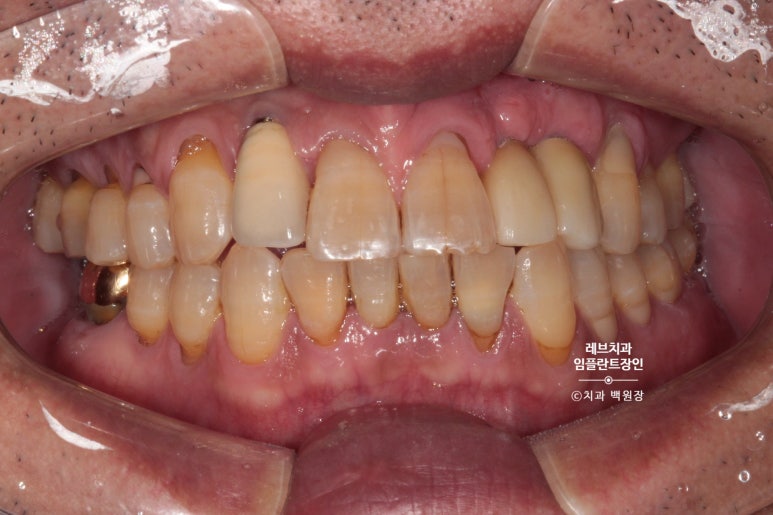

보시면 임플란트 주변으로 깔끔하게 잇몸이 아문 것을 보실 수 있죠?

그리고 또 하나의 변화! 기다리는 3개월의 치유기간동안 치아목의 충치들을 깔끔하게 치료해드렸습니다!

약~간 티가 나긴 하지만, 환자분은 매우 만족해하셨다는 후문.

그리하여 유사하게 만들어본 앞니입니다.

왼쪽 위 작은 앞니와 송곳니를 합쳐서 2개짜리 보철물을 만들었어요!